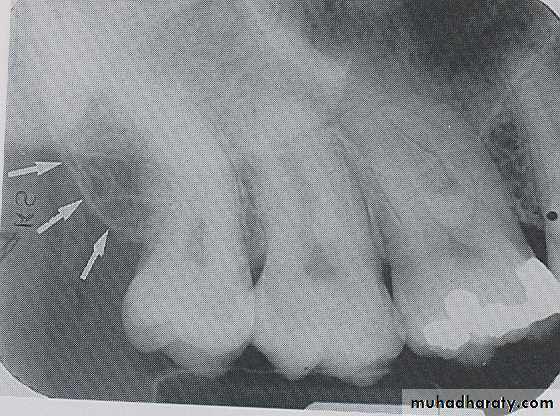

NUTRIENT CANALS

:

Nutrient canals carry a neurovascular bundle and appear as radiolucent lines of fairly uniform width. They are most often seen on mandibular periapical radiographs running vertically from the inferior dental canal directly to the apex of a tooth or into the inter dental space between the mandibular incisors.